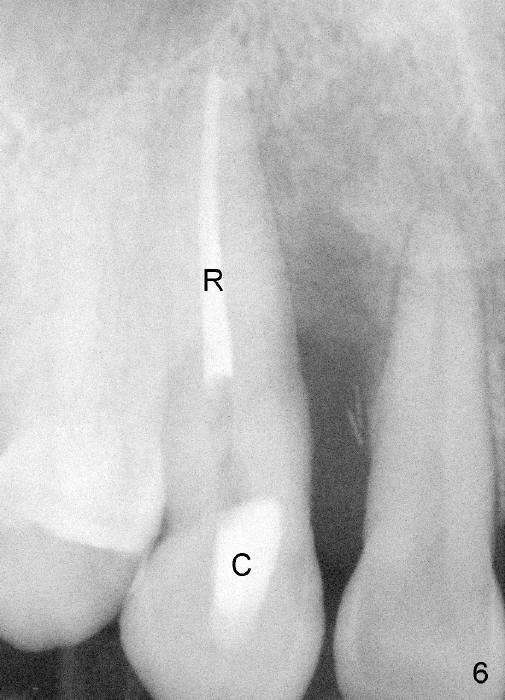

A male patient had trauma to the tooth #6 at the age of 13.  The affected tooth has remained asymptomatic for more than 30 years (Fig.1).   X-ray reveals an oblique root fracture (Fig.2 >) with radiolucency in the mesial alveolus (*, apparently normal trabecular pattern).  Six years later (Feb. 2011), an acute infection develops (Fig.4 *).  It requires incision & draining and antibiotic.  At that time, the trabecular pattern disappears around the fracture line mesially (Fig.3 *).  Four months later cone beam CT shows bone loss between #6 and 7 (Fig.5 *).  Root canal therapy is done as a palliative measure (Fig.6 R; C: Cavit).  Three months later, MTA (mineral trioxide aggregate) is placed in the coronal canal next to the fracture line (Fig.7 M).  It is hoped that MTA can promote nearby bone and cementum to regenerate to seal the fracture line.  Four months after MTA application, there is no sign of bone regeneration (Fig.8).  Bone is lost for approximately 7 mm.